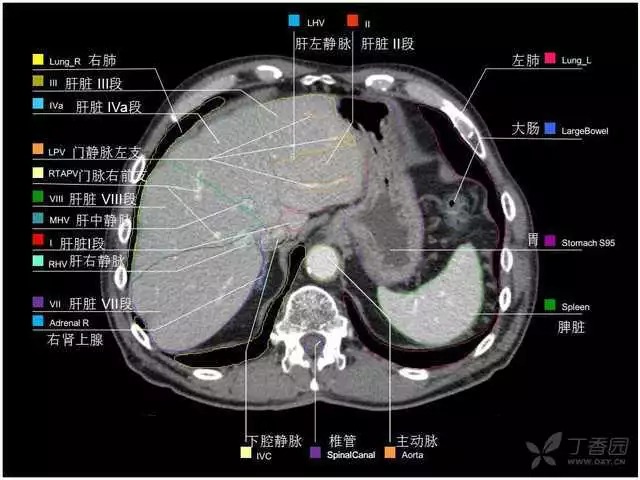

腹部肝脏高清CT断层的图谱

全腹部高清CT图谱,淋巴结彩色图谱,血管解剖图谱大汇总!

肝段,肝内管道的分布规律

美国放射学会ACR官网,对肝脏的区域和节段解剖学概述